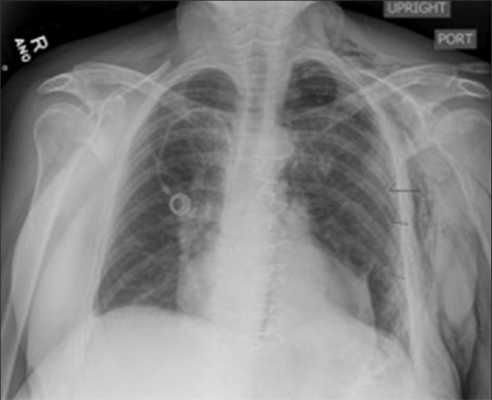

Рентгенологический контроль положения центрального катетера

После катетеризации внутренней яремной или подключичной вены необходимо произвести рентгенографию органов грудной клетки для подтверждения правильного расположения катетера и исключения пневмоторакса. Если больному проводится ИВЛ - рентгенография проводится сразу после катетеризации. При самостоятельном дыхании больного - через 3-4 часа. При признаках гемоторакса, пневмоторакса - рентгенография проводится немедленно.

Определение правильного положения дистального конца катетера на ретгенограмме

На рентгенограмме грудной клетки в передней проекции у взрослых конец катетера должен располагаться не более чем на 2 см ниже линии, соединяющей нижние концы ключицы. Эта линия разделяет верхнюю полую вену на два участка, расположенных ниже верхней границы перикарда и выше нее. Если катетер вводят в нижнюю полую вену, его конец должен располагаться ниже уровня диафрагмы.

Катетер вводят до уровня соединения 2 ребра с грудиной, что соответствует впадению полой вены в правое предсердие. После установки ЦВК рекомендуется сделать рентгенограмму грудной полости, чтобы исключить пневмоторакс на стороне пункции и уточнить расположение кончика катетера в верхней полой вене.